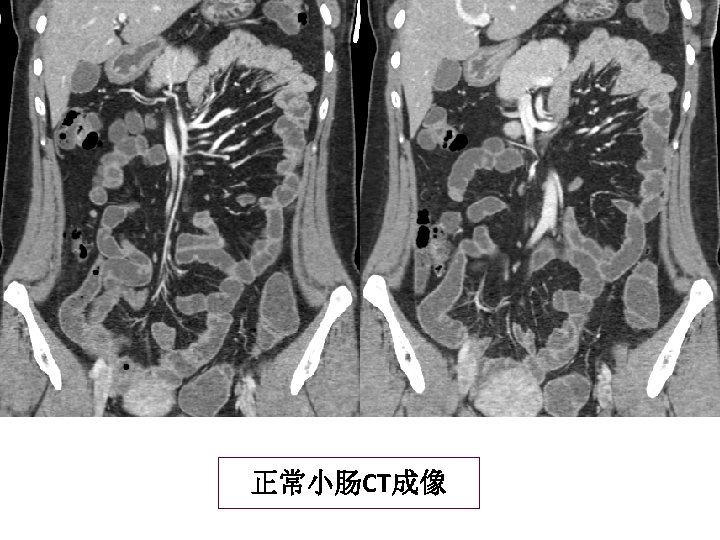

Target sign A 27 -year-old male presented with abdominal pain of 10 hours duration

Target sign A 27 -year-old male presented with abdominal pain of 10 hours duration 肠系膜上静脉血栓形成